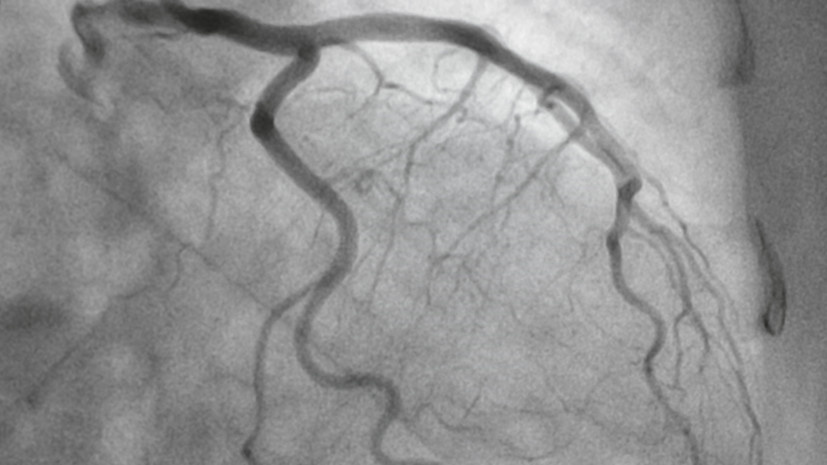

Главный врач диагностического отделения АО «Медицина» (клиника академика Ройтберга), врач ультразвуковой диагностики высшей категории, член Европейской ассоциации ядерной медицины Оксана Платонова рассказала, в каких случаях проводят ангиографию. «Эту процедуру проводят только при необходимости, если у пациента был инфаркт, инсульт или другое сердечно-сосудистое заболевание», — заявила она в беседе с «Газетой.Ru». По её словам, ангиография высокоинформативна, но требует строгих показаний и учёта накопленной дозы. Ранее врач-кардиолог Ольга Савонина в беседе с сайтом «Москва 24» рассказала, что на ишемический инсульт приходится примерно 80% случаев.

По её словам, ангиография высокоинформативна, но требует строгих показаний и учёта накопленной дозы.